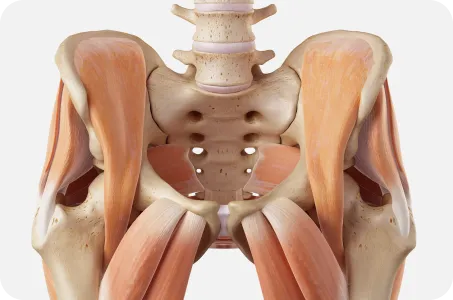

골반이 틀어지면

온몸이 무너진다.

골반은 보행시 지면에서 올라온 충격을 척추로 전달하고

상체의 무게를 고관절과 하지로 전달하는 역할을 하기 때문에

힘전달의 중심축의 역할을 합니다.

골반이 틀어지면 척추와 어깨, 고관절, 무릎이 같이 틀어집니다.

▲ 힘 전달의 균형 유지

▲ 힘 전달의 균형이 깨질 때

골반은 허리와 다리를 연결하는 상하체 균형의 핵심 역할을 합니다.

우리의 몸은 한 곳이 틀어지면 연결되어있는 다른 곳도 틀어질 수 있습니다.

따라서 거북목, 일자목, 굽은등, 허리뼈의 틀어짐은 골반부터 교정해야 진도가 나갈 수 있습니다.

요추 –골반- 고관절 복합체인 3개의 축을 동시에 교정하니까

골반은 위로는 척추와 어깨, 아래로는 고관절 및 발, 무릎까지 연관이 있습니다. 틀어진 골반만 교정하는 것이 아니라 골반틀어짐으로 인해 생긴 척추와 고관절 무릎까지 넓게 보고 교정하기 때문에 골반교정으로 몸 전체의 척추관절이 교정되는 효과를 볼수 있습니다.